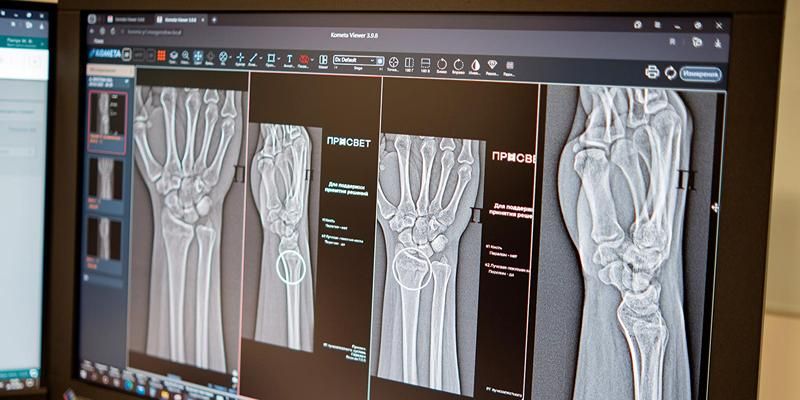

В Москве начали работать два новых сервиса на основе искусственного интеллекта (ИИ) для высокоточной диагностики множественных переломов голеностопного и лучезапястного суставов. Эти травмы способны привести к неправильному сращению костей, деформациям и нарушению подвижности. Благодаря цифровым инструментам в лучевой диагностике теперь врачи смогут быстрее и точнее оказывать помощь. Искусственный интеллект уже применяют в 43 клинических направлениях. Об этом сообщила Анастасия Ракова, заместитель Мэра Москвы по вопросам социального развития.

«Цифровые решения уже более пяти лет помогают столичным рентгенологам — прежде всего, в анализе медицинских снимков. Недавно мы запустили два новых ИИ-сервиса, которые помогают обнаруживать на рентгеновских изображениях травмы костей голеностопного и лучезапястного суставов — одних из самых функциональных и при этом уязвимых. Алгоритмы автоматически отметят поврежденные участки и выполнят необходимые измерения, даже если на снимке присутствуют признаки сразу нескольких переломов. Сегодня в распоряжении московских рентгенологов уже более 60 ИИ‑сервисов. Одни отличают норму от проявления заболевания, другие, например, могут измерять границы и размеры патологии. Сервисы применяются по 43 клиническим направлениям. В условиях большого потока пациентов технологичные ассистенты помогают сохранять высокое качество и скорость диагностики для каждого жителя столицы», — рассказала Анастасия Ракова.

Основными симптомами перелома являются отек и боль, которая обостряется при движении. Для минимизации негативного влияния и сохранения мобильности поврежденных суставов необходима быстрая и точная диагностика, включающая оценку масштабов травмы. ИИ-технологии в лучевой диагностике анализируют снимки по множеству параметров, помогают выполнить необходимые расчеты и позволяют ускорить описание снимка. Они могут заметить даже минимальные трещины и обратить внимание врача на то, что в этой области не один, а несколько переломов. Правильно выявленные обстоятельства позволяют выбрать подходящую тактику лечения.

«Травмы предплечья, кисти и голени встречаются достаточно часто. Диагностика перелома включает осмотр травматолога с последующим выполнением рентгенографии. Специалисты используют ИИ-алгоритм как инструмент, способный повысить точность и скорость анализа лучевого изображения, что критически важно для постановки диагноза. Своевременная диагностика позволяет оперативно назначить лечение и избежать осложнений. В результате у пациентов быстрее восстанавливается подвижность и появляется возможность вернуться к активной жизни», — добавил главный внештатный специалист по лучевой и инструментальной диагностике Москвы Юрий Васильев.